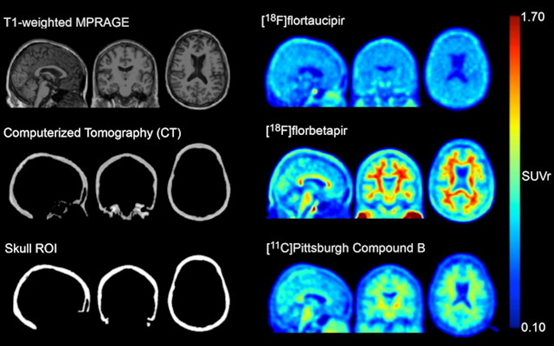

該小組首先從CT掃描中創(chuàng)建了“頭骨面具”,以定義313名認知正常和輕度受損的男性(n = 196)和女性(n = 177)的感興趣區(qū)域(ROI)。所有受試者都接受了淀粉樣蛋白PET (F-18 florbetapir和Pittsburgh compound B)和tau PET成像,作為他們參與試驗的一部分。

然后使用這些面罩來量化flortaucipir F-18 (Tauvid,Avid Radiopharmaceuticals)受試者的顱骨攝取,這是最廣泛使用的tau PET示蹤劑。

高放射性示蹤劑頭骨結(jié)合的淀粉樣蛋白陰性參與者的MR、CT和標準化攝取值比率(SUVr)圖像。圖像在MNI-152空間。圖片由《核醫(yī)學雜志》提供。

一項分析顯示,313次flortaucipir F-18掃描中有50次(16%)具有高水平的顱骨信號。大多數(shù)是女性(n = 41,82%),在女性中,較低的顱骨密度與較高的flortaucipir F-18顱骨信號相關(guān)。根據(jù)結(jié)果,頭骨信號與其他已知的非目標區(qū)域基本上沒有關(guān)聯(lián),并且在縱向掃描中是一致的。